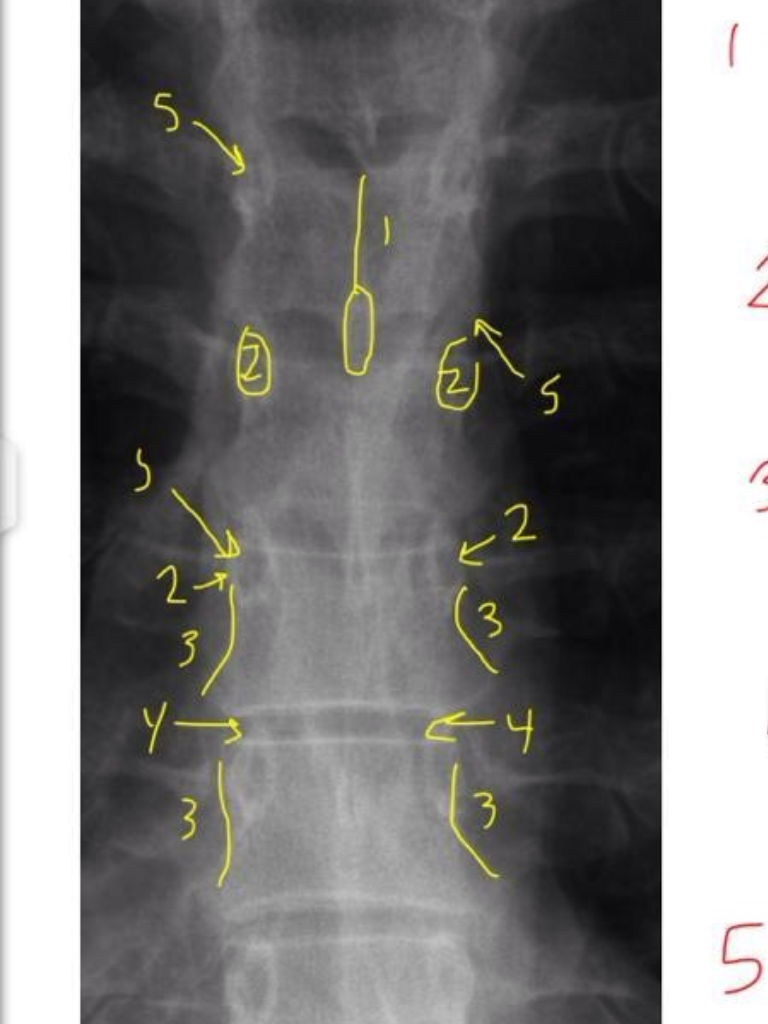

7

1

A

Ocipital Condyles

8

2

Foramen Magnum

9

3

Lateral Masses of C1

10

4

C1 TVP/Lateral Mass Junction

11

5

Odontoid Process

12

6

C2 Spinous Process

13

C2 Pedicle shadow